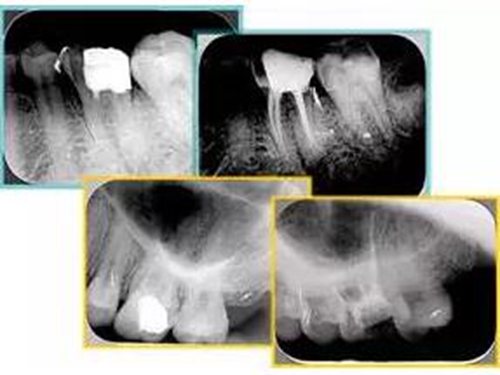

6. 術(shù)后 X 線片

術(shù)后 X 線片用來評(píng)定根管充填 長(zhǎng)度、致密度(管壁清晰、側(cè)枝)等指標(biāo)。

15.jpg

左圖為根管充填術(shù)后 X 線片。圖中可見,根管充填較好。右下圖有白色小點(diǎn),為側(cè)方加壓導(dǎo)致糊劑擠出所致,表明根管充填比較致密。

致密、恰到好處的充填可去除干凈根管里感染灶,機(jī)體逐漸恢復(fù)。

16.jpg

多根牙時(shí)候需進(jìn)行偏移投照,正位投照無法說明具體哪根牙根管充填效果。